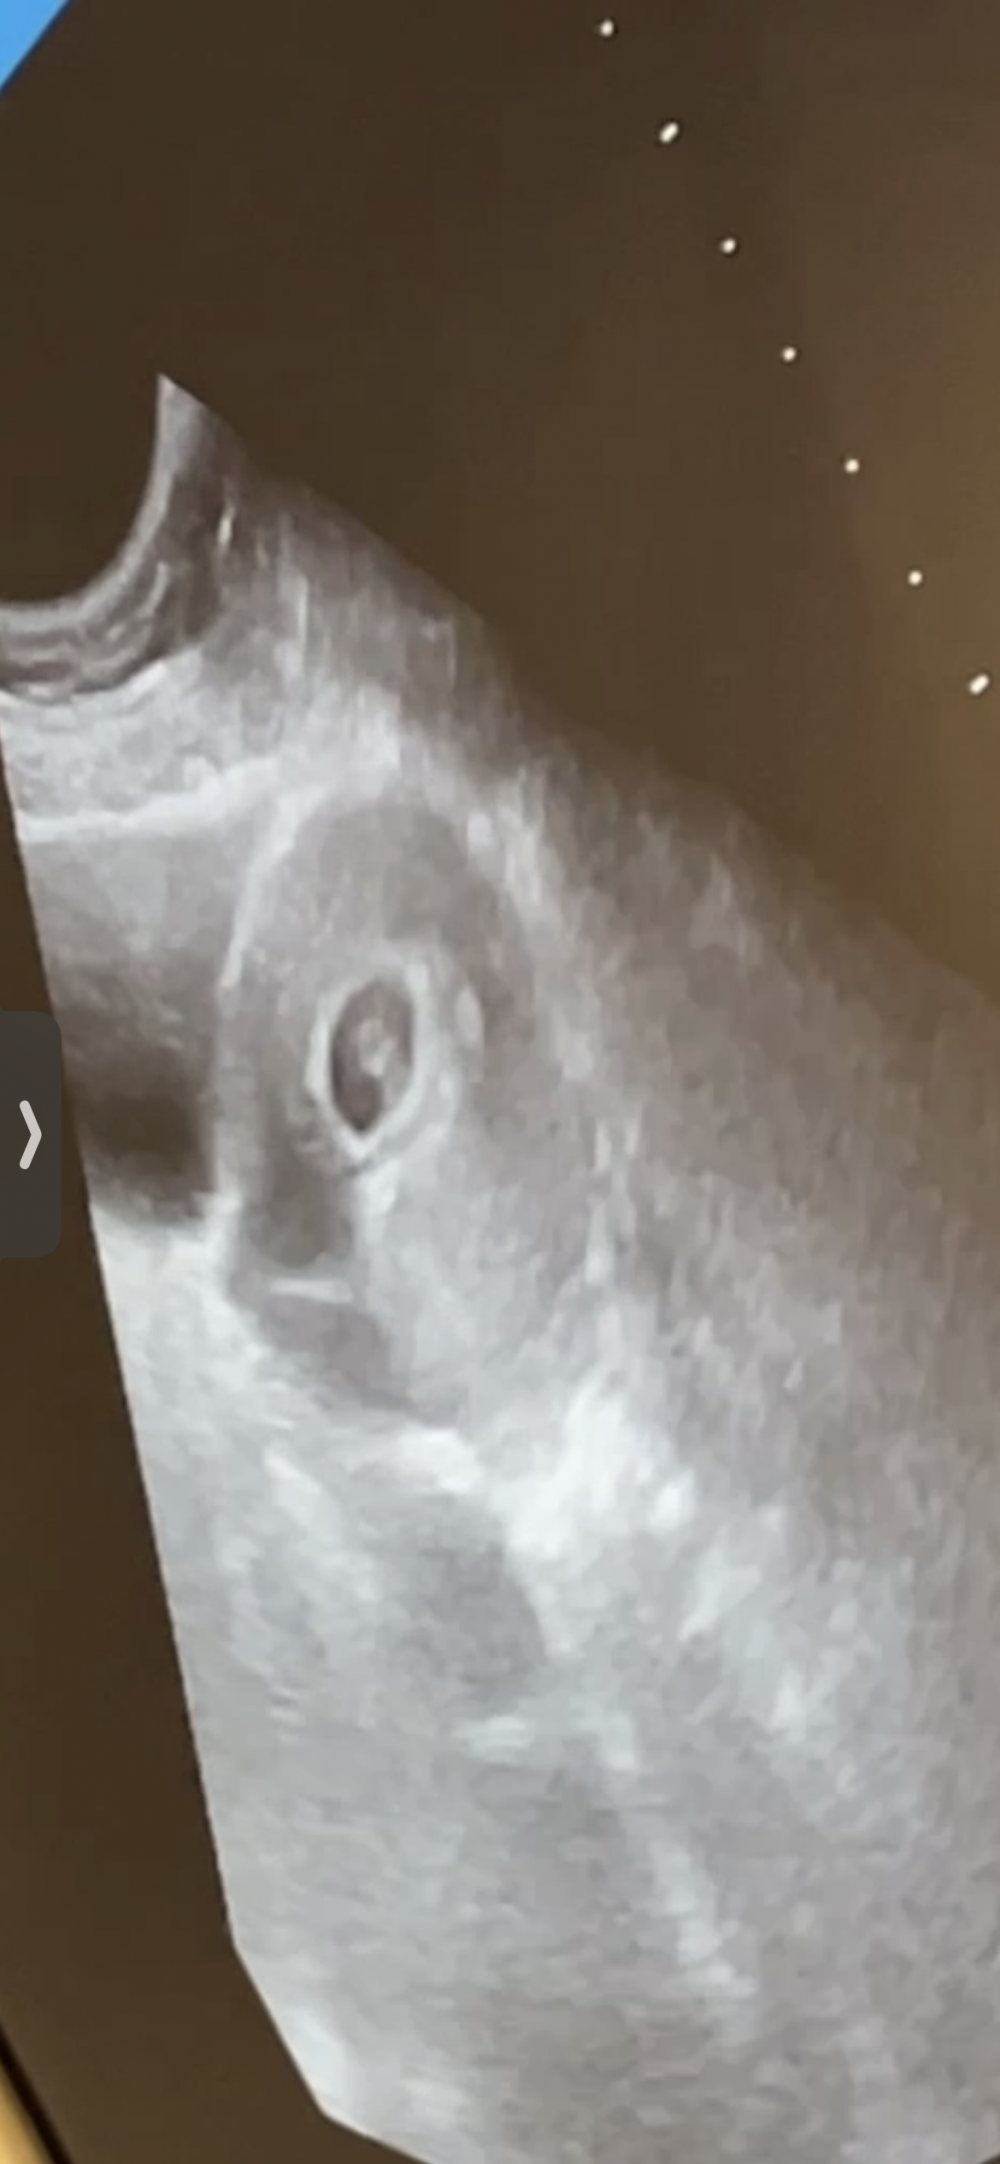

سارونه على نظرية رامزي يفرق اذا سونار بطني او مهبلي ؟

كيف تحليلك 🤣